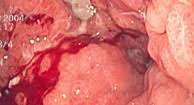

Treatment Strategies In Gastric Cancer 14 10 2011 from www.aerzteblatt.de Stage iii b is characterized by the growth of the tumor outside the stomach lining. If it is stomach cancer, however, the blood is likely related to inflammation caused by cancer, and tends to show up in more advanced stages of the disease, though it can also show up earlier on. When the signs and symptoms of stomach cancer are not apparent, the disease may reach advanced stages before a diagnosis is made. Stomach cancer is an abnormal growth of cells that begins in the stomach. Symptoms exhibited in advanced stages include: Discomfort or pain in the upper or middle part of the abdomen blood in the stool, which appears as black, tarry stools vomiting or. Symptoms of more advanced stomach cancer include: Main symptoms of stomach cancer.

Stomach Cancer Causes And Treatment Cancer Specialist Zeeva Clinic from i0.wp.com Because stomach cancer often causes no symptoms in its early stages, some people find out that their cancer is advanced when it is first diagnosed. If the blood is fresh and red, it is more likely to have come from a tear in the large intestine or anus. ) vomiting (the vomit may be streaked with blood), although this is uncommon in the early stages. Feeling full very quickly when eating; In more advanced stages of gastric cancer, the following signs and symptoms may occur: There are iv stages of stomach cancer and the disease is classified according to several factors. The stomach is a muscular sac located in the upper middle of your abdomen, just below your ribs. Advanced stomach cancer means that a cancer that began in the stomach has spread to at least one other part of the body, such as the liver or lungs.